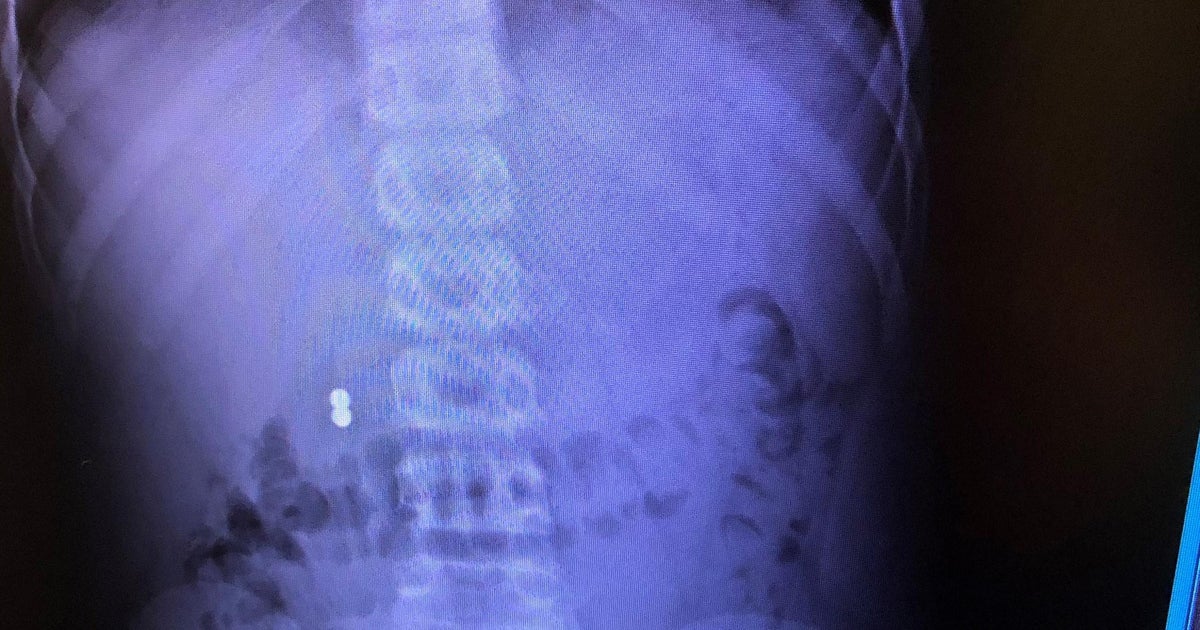

Doctors warn danger of children swallowing New York Daily News Magnets Babies Danger When two or more magnets. The magnets, or a magnet and another metal object, stuck to each other, even through folds of intestine or tissue. Sets of tiny, strong magnets were sold as adult toys but often were swallowed by children, resulting in serious injury and even death. Because damage caused by magnets can be serious, it’s. A potentially life. Magnets Babies Danger.

danger Mom shares warning after son swallows Magnets Babies Danger The magnets, or a magnet and another metal object, stuck to each other, even through folds of intestine or tissue. Because they are small, children may swallow. Sets of tiny, strong magnets were sold as adult toys but often were swallowed by children, resulting in serious injury and even death. When two or more magnets. A potentially life threatening tiktok. Magnets Babies Danger.